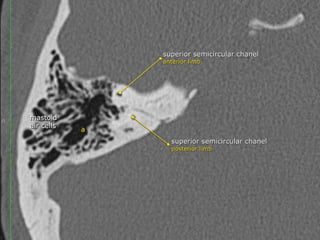

 Superior (anterior) semicircular canal (SSCC)

orientated in the vertical plane perpendicular (transverse) to the long axis of the

PTB. it lies under the arcuate eminence on the anterior surface of the PTB. Hair

cells of the superior semicircular duct supplied by the superior division of the

vestibulocochlear nerve (CN VIII). Seen perpendicular to long axis of

temporal bone

 Posterior semicircular canal (PSCC)

orientated in the vertical plane parallel to the long axis of the PTB

hair cells of the posterior semicircular duct supplied by the inferior division of CN

VIII